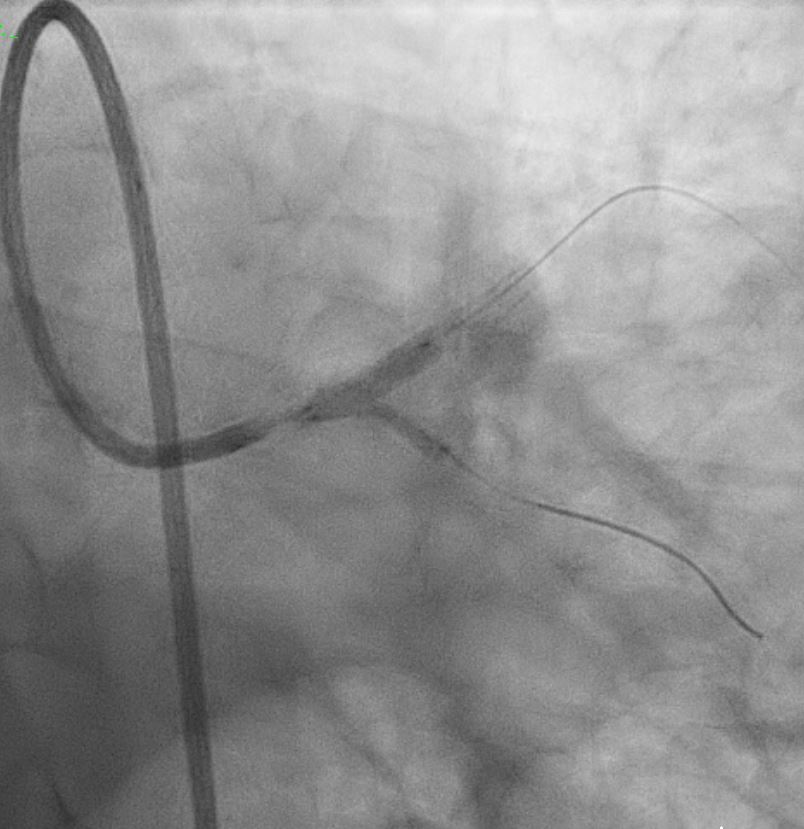

Right Radial approach, Slender 6/7Fr , EBU 3.5 7FR changedto EBU 3.0 7FR Sion blue to LCX, Run-through floppy to LAD IVUS run to LAD Fibro calcified lesion ostial LAD - calcium arc 180 degrees with calcium nodule, ostial LAD 3.48mm2 , tightest proximal LAD 2.31mm2 distallumen size 3.0mm and proximal 3.5mm and ostial 4.0mm ostial LM MLA 10.8mm Used microcatheter fine cross to LAD , Exchange with balloon trapping withRotaWireRotablator 1.5burr introduced- 2 runs high speed 180kph and2 runs at 80kph IVUS done post Rotablator - tightest proximal LAD 2.31mm2 -->3.22mm2 , ostial LAD 3.48mm2 -->4.51mm2 Predilate further NC 3.5x15mm up to 16atm Stented Synergy monorail 3.0x32mm body LM to proximal LAD at11atm with guide plus 6FRpost dilated NC 3.5x12mm up to 20atm Guiding catheter slipped out and lost the system, tried to reengage but challenging thus decided to change to right femoral puncture to use EBU3.5/7fr ,post dilate LM-LAD NC 4.0/12mm 6atmOstial LCX pinched - decided for Kissing balloon inflation and DCB LCX ostium predilated Ostial LCX 2.75x15mm up to 8atm Kissing inflation performed with NC emerge 3.5X15mm LAD, NC2.75x12mm in LCX 8atm DCB AGENT MONORAIL 2.75X15 MM 8atm 60seconds to ostial LCX last POT with NC 4.0x12mm up to 16atm IVUS done stent well opposed, Ostial LAD MSA 8.25mm2Proximal MSA 5.64mm2 TIMI III flow

In summary, this was a complex PCI for a severely fibro-calcified ostial and proximal LAD lesion with significant calcium arc and a calcium nodule confirmed on IVUS. Despite initial right radial access with a Slender 6/7 Fr system, guide support with EBU 3.5 and later EBU 3.0 remained suboptimal, ultimately necessitating conversion to a right femoral 7 Fr approach for adequate support. Overall, the case highlights the importance of adaptive access strategy, aggressive plaque modification, IVUS-guided optimization, and bifurcation management to achieve an excellent final physiological and angiographic result in a heavily calcified LM–LAD lesion.